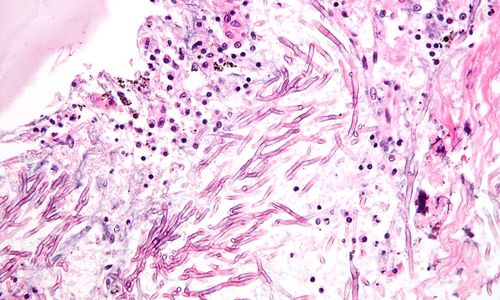

Pulmonary aspergillosis - jeden z mnoha původců mykózy.

Autor snímku Nephron